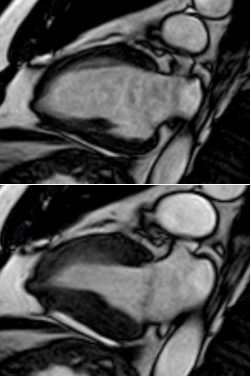

RESO: Left ventricle with preserved volumes and mass. At the apex level there is a microaneurysm (saccular evagination, "gloved finger", of the myocardial wall, which is severely thinned: 1.5mm and dyskinetic). Normal parietal motility of the rest of the segments. Preserved systolic function. Late enhancement sequences do not show gadolinium uptake.

Figure 4 Post-gadolinium late enhancement sequence: Due to the extreme thinning of the aneurysm wall, no significant gadolinium uptake is identified.